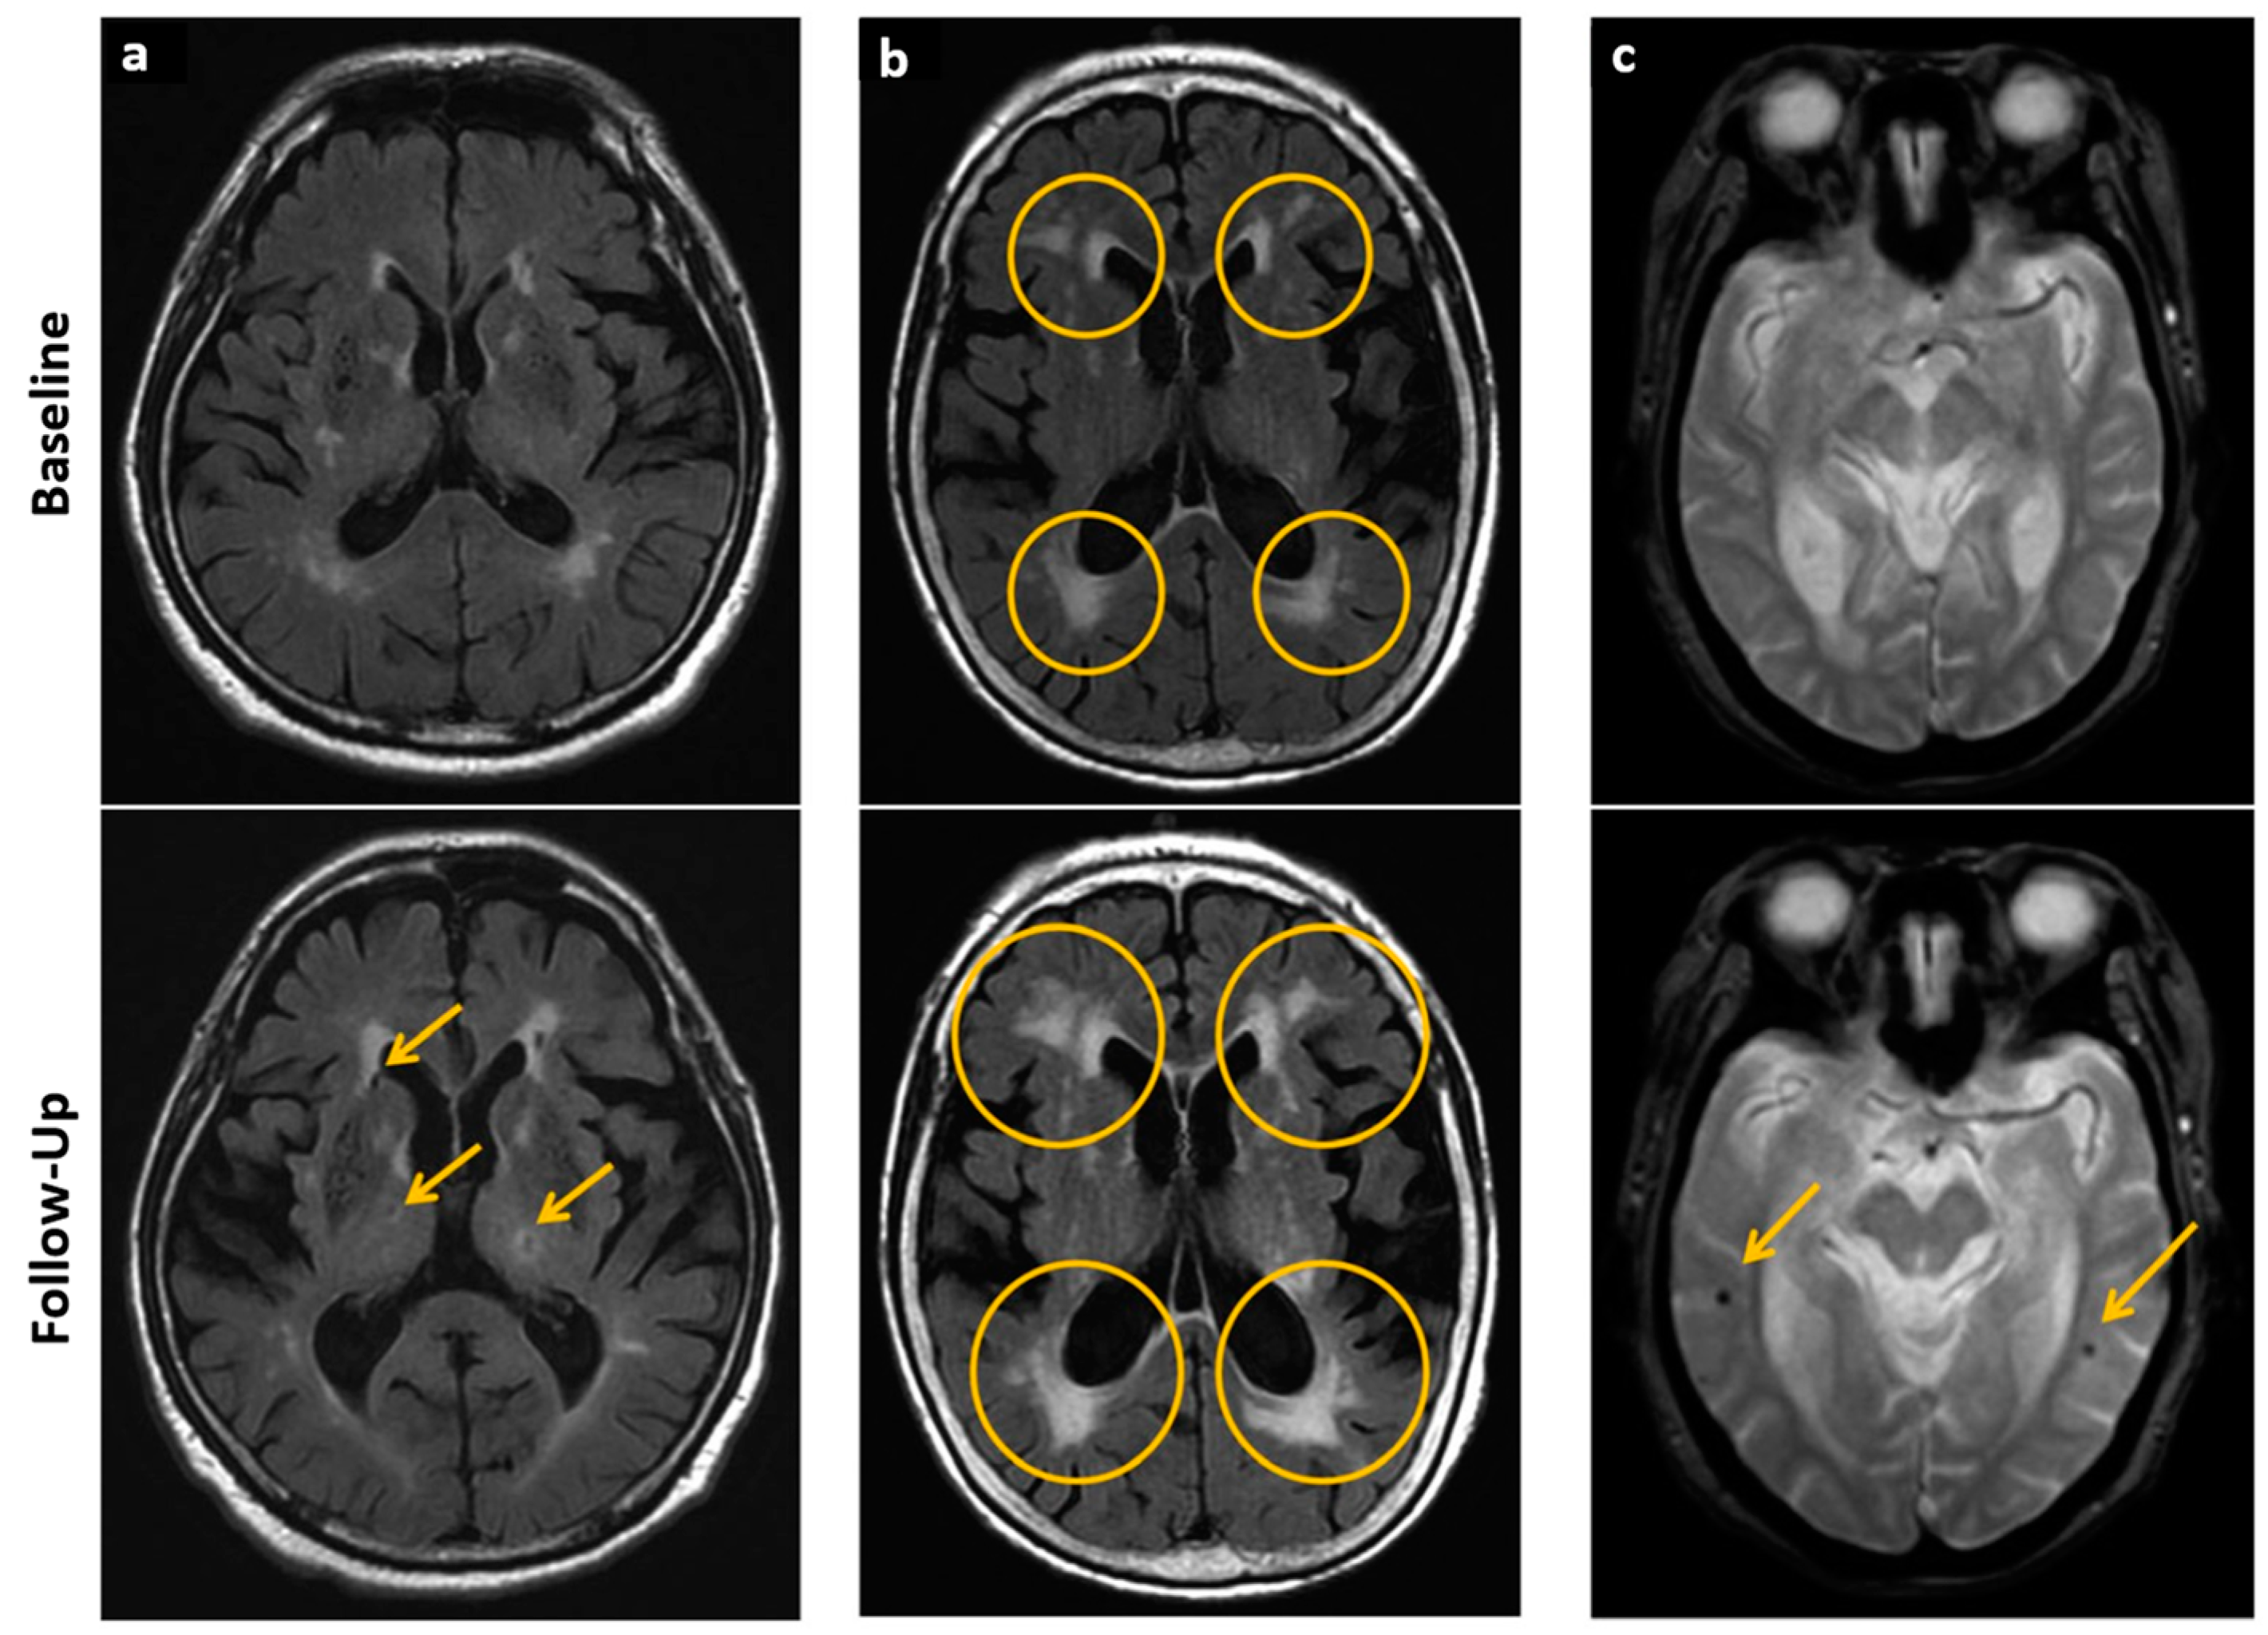

- Umemura, T.; Kawamura, T.; Hotta, N. Pathogenesis and neuroimaging of cerebral large and small vessel disease in type 2 diabetes: A possible link between cerebral and retinal microvascular abnormalities. J. Diabetes Investig. 2017, 8, 134–148. [Google Scholar] [CrossRef] [PubMed]

- Biessels, G.J.; Reijmer, Y.D. Brain Changes Underlying Cognitive Dysfunction in Diabetes: What Can We Learn From MRI? Diabetes 2014, 63, 2244–2252. [Google Scholar] [CrossRef]